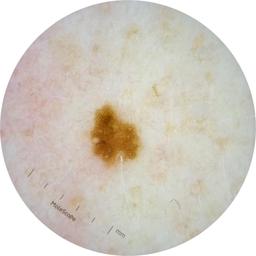

ISIC_2261268

acquisition_day 307

age_approx 50

anatom_site_1 Trunk

anatom_site_2 Posterior trunk

anatom_site_general posterior torso

diagnosis_1 Benign

diagnosis_confirm_type single image expert consensus

image_type dermoscopic